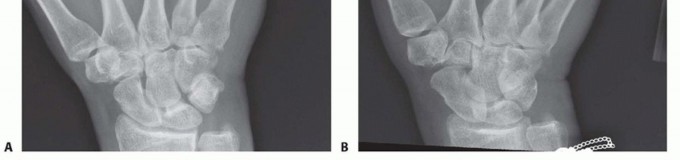

Clinical & Radiographic Imaging Archive